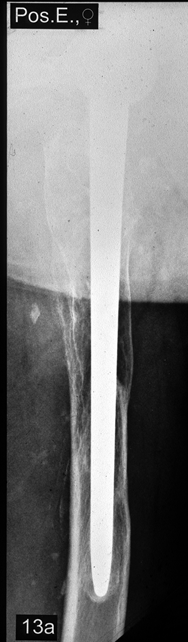

Abb. 13

Die Abbildung

zeigt die einzelnen Schaftsysteme für die

unterschiedlichen Indikationen: SL-PLUS® Schaft (links)

für die Primärimplantation, SLR-Revisionsschaft (Mitte)

für Revisionseingriffe, Modularschaft (rechts) für

komplizierte Revisionseingriffe mit großen

Knochendefekten |